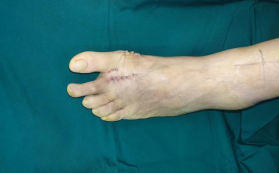

在足踝外科石荣剑副院长、徐明亮主任手术团队的密切配合下,用时一个小时左右,成功为王阿姨实施了左足第2跖趾关节人工关节置换术+拇外翻矫形术。

术后即刻

目前,王阿姨恢复得很好,已经进入康复阶段,家属也对治疗效果非常满意。